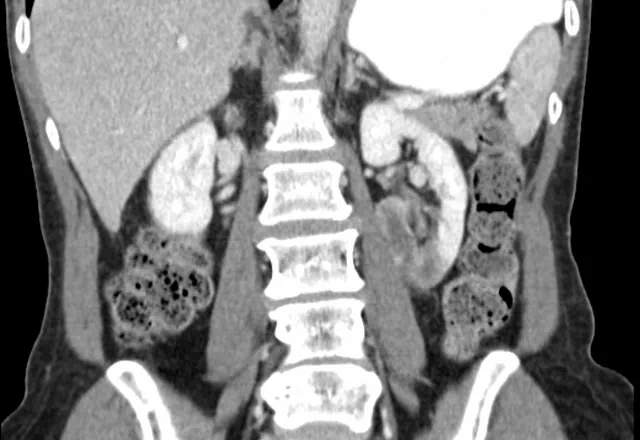

The diagnosis of renal infarction is suggested by an elevated LDH. The diagnosis itself is typically made with computed tomography. The image above is typical. A wedge shaped lesion that does not enhance with contrast is seen. The extent of the infarction depends on which renal artery was occluded and at what level.

When reviewing the CT images it is important to look for renal artery abnormalities that may explain the event. These include segmental arterial mediolysis, renal artery dissection and renal artery aneurysm. Specifically, look for signs of FMD. If you can’t find a cause within the renal artery, some experts recommend a carotid artery ultrasound to look for fibromuscular dysplasia there.